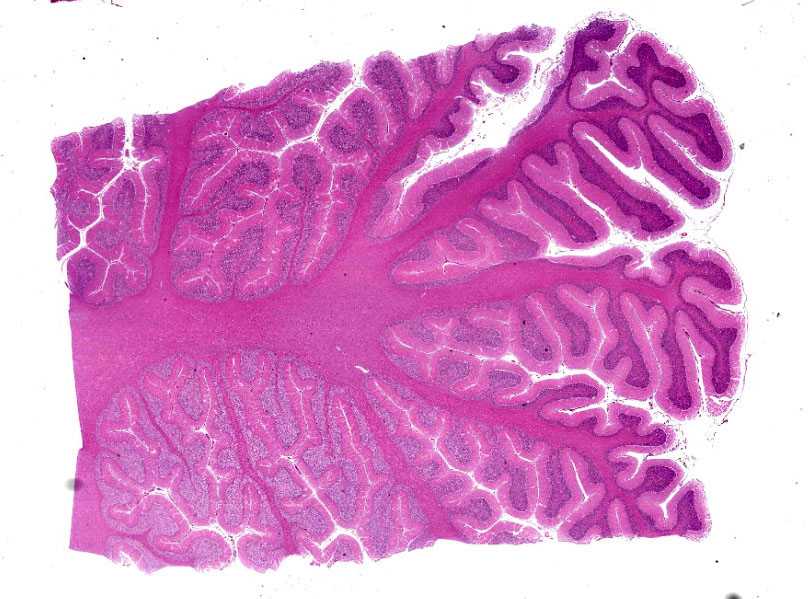

Cerebellum: Multifocally, numerous Purkinje cells at the junction between the molecular and granule cell layer, as well as occasional neurons within the granular cell layer and cerebellar deep nuclei are moderately swollen, have pale granular eosinophilic to clear, finely vacuolated or foamy cytoplasm that often dis-places the nuclei towards the periphery. Neurons are multifocally lost within the Purkinje (empty baskets) and granular layers. Through-out the white matter tracts, there are numerous variably sized (up to 60 μmin diameter) hypereosinophilic axonal swellings (spheroids) as well as less frequent dilation of periaxonal spaces containing fragmented myelin debris (ellipsoids) and foamy macrophages (digestion chambers). Multifocally, few axonal swellings are also present within the granule cell layer (torpedoes).

Cerebellum: Neuronal vacuolation and loss, diffuse, severe with occasional neuronal intracellular granular eosinophilic material ac-cumulation, torpedoes, spheroids and digestion chambers (Wallerian degeneration).

Cerebellum: Neuronal vacuolation and loss, chronic, diffuse, severe, with axonal swelling.